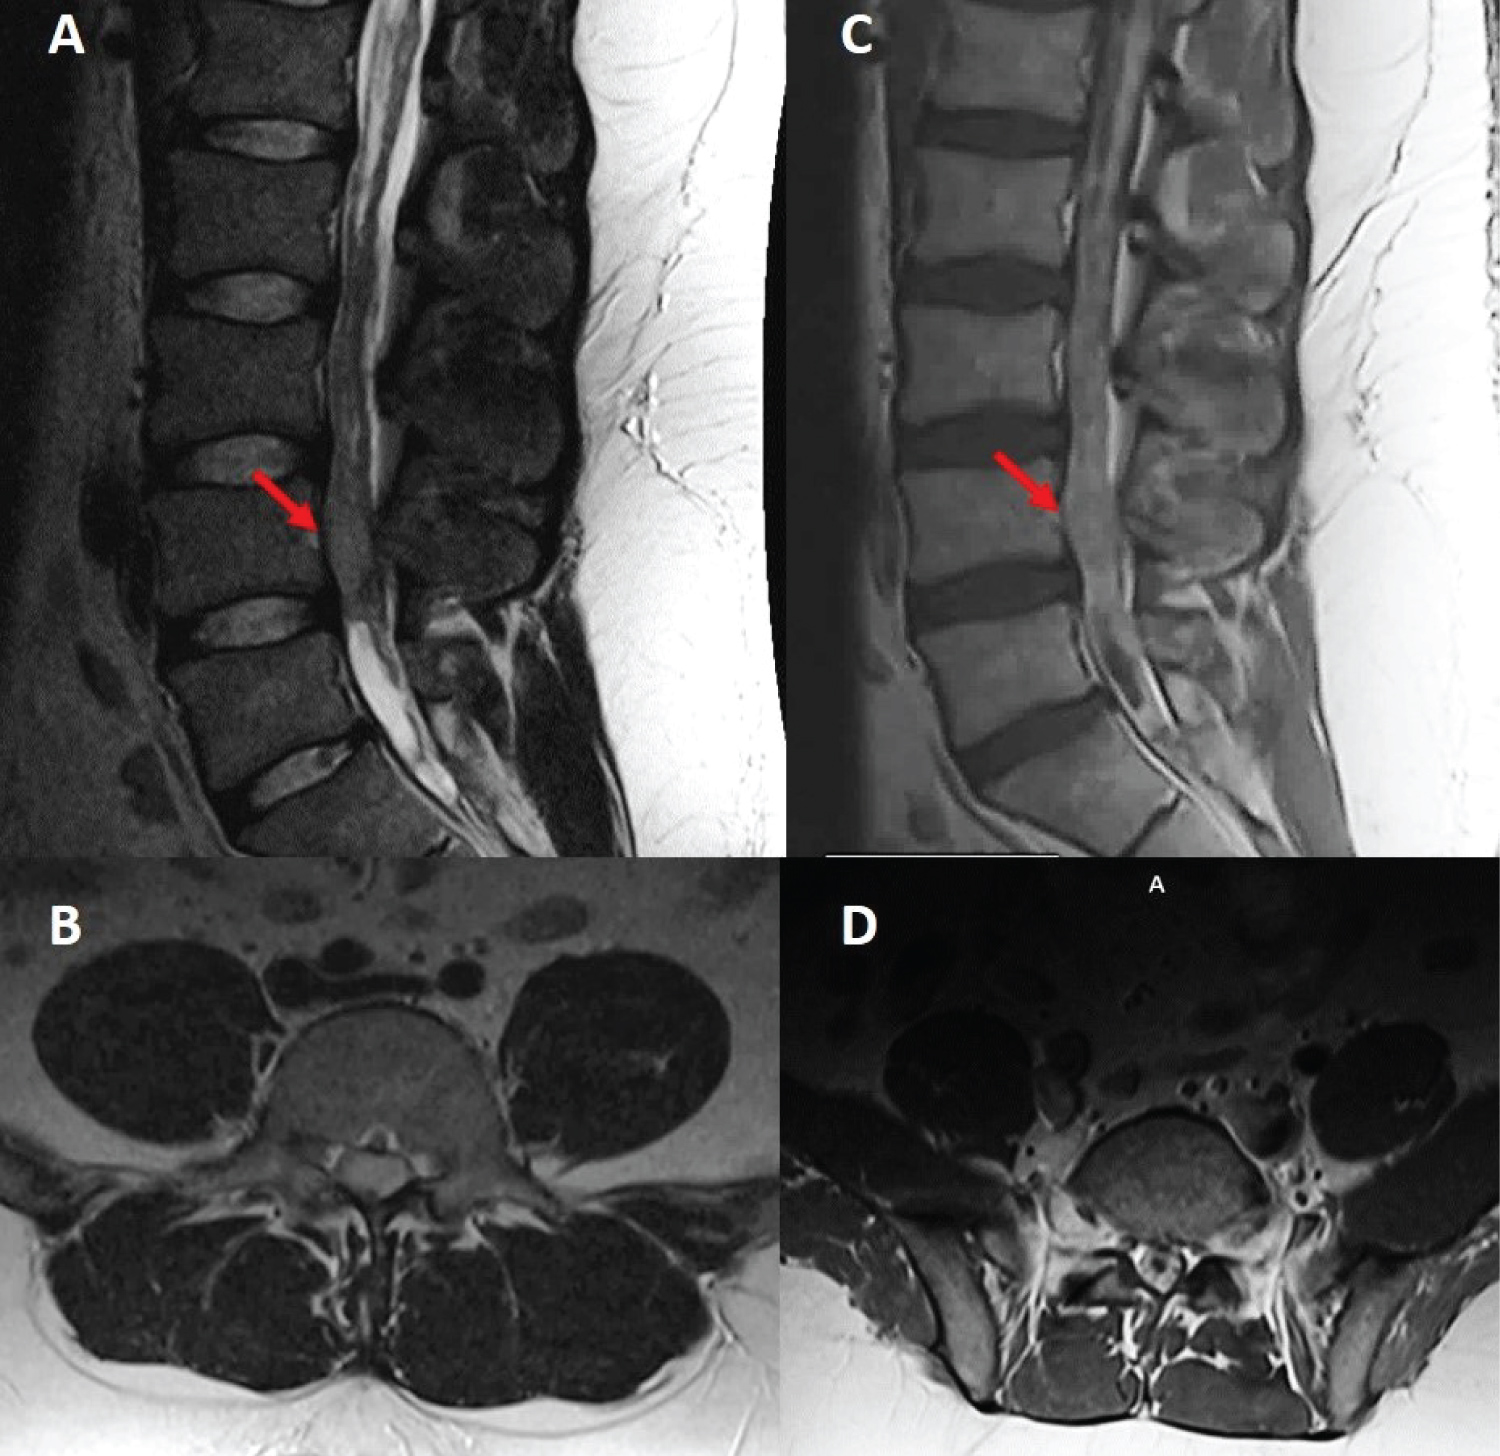

A 26-year-old male with no significant past medical history presented with lower back pain, progressive lower extremity weakness with paresthesias and difficulty voiding over a period of several months. Magnetic resonance imaging (MRI) of the lumbar spine revealed an intradural extramedullary mass at the L4 level. Subsequent imaging of the neural axis revealed extensive abnormal surface enhancement of lower thoracic cord, a small linear focus along posterior margin of the cord at C3-4 disc space, and a foci of enhancement within the posterior fossa (Figure 1). These findings were concerning for leptomeningeal metastatic disease. The patient underwent surgical intervention with L4 laminectomy and L3 partial laminectomy for open biopsy and resection of the lumbar spine lesion, with resection of a 2 × 5 cm cauda equina mass. Intraoperatively, the cauda equina roots were notably expansile and matted together due to tumor infiltration. There was additional metastasis noted throughout the lumbar spine within the subarachnoid space as well as nerve roots. Final pathology described an INI-1 deficient malignant neoplasm with an immunophenotype suggestive of AT/RT.

Figure 1: Sagittal (A) and axial (B) T2, sagittal (C) and axial (D) T1 post-contrast MRI sequences demonstrating an intradural and extramedullary lesion centered at the L4 level of the lumbar spine (red arrows). View Figure 1